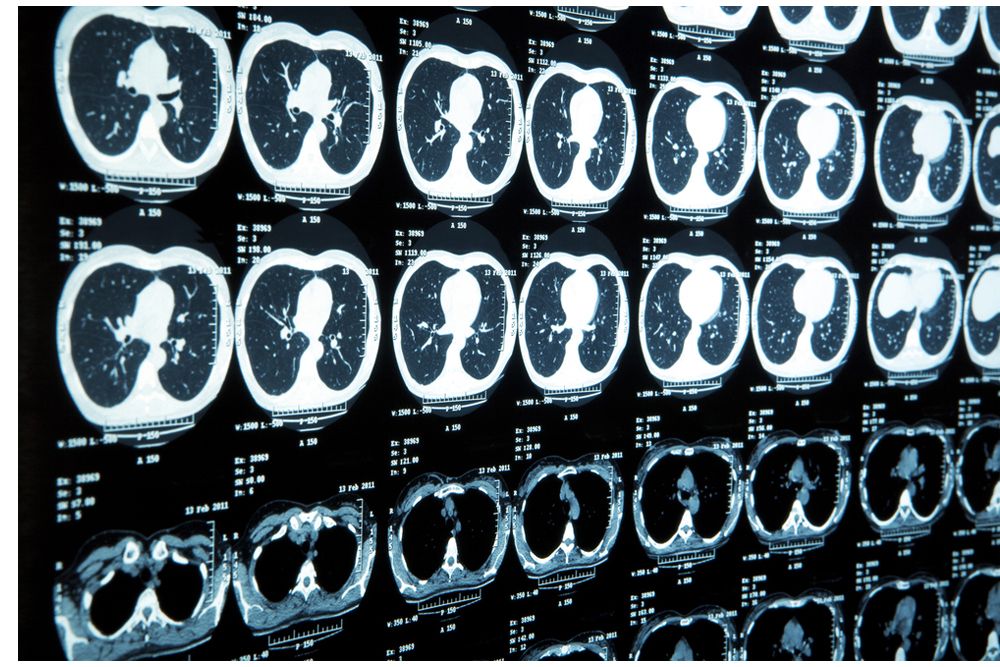

Brain CT and MRI for early stage lung cancer patients are not routinely recommended.